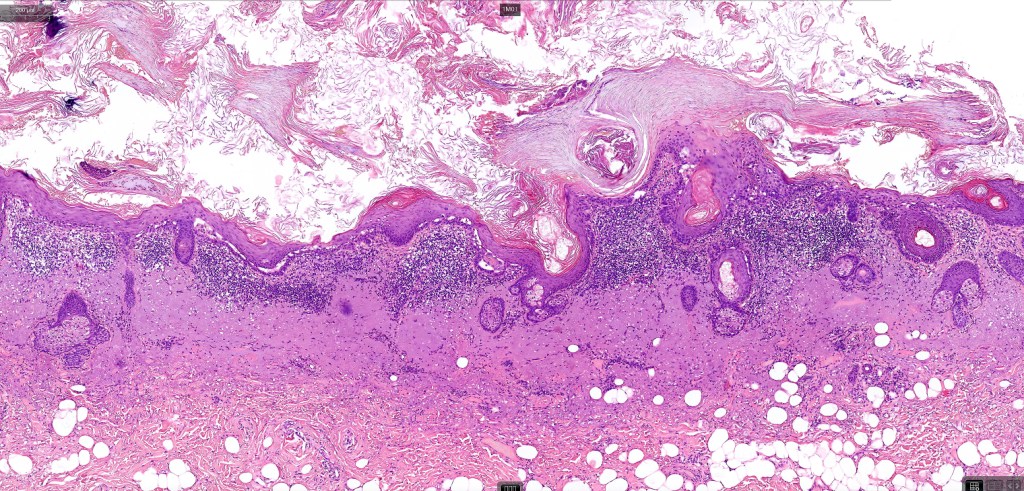

Histological features

•Although a variety of subtypes are recognized, all are characterized by varying degrees of epidermal dysplasia

•Hyperkeratotic/hyperplastic actinic keratosis represents the prototype-alternating hyperkeratosis & parakeratosis- the former overlies the follicular & sweat duct ostia (Freudenthal funnel) while the latter overlies the interadnexal dysplastic epithelium & ranges from basal cell layer though to full thickness dysplasia (Bowenoid actinic keratosis); budding from the epidermis is a common finding; dysplastic epithelium commonly forms a mantle around the follicles and superficial sweat ducts

•Solar elastosis

.Superficial dermal lymphohistiocytic infiltrate